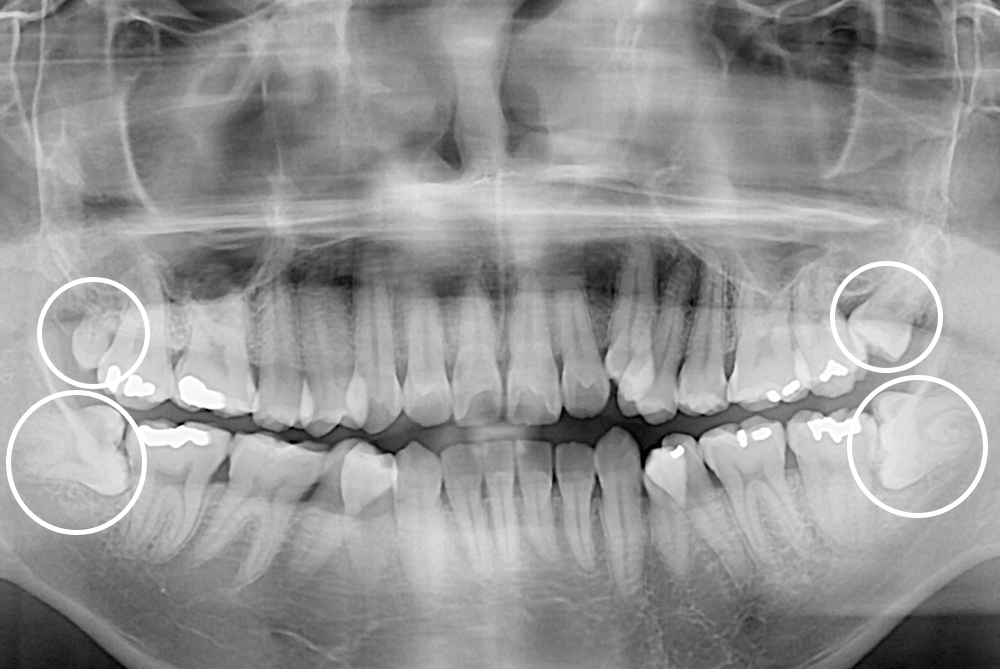

[사랑니] 매복 사랑니 발치

치료전 : 2017-08-08